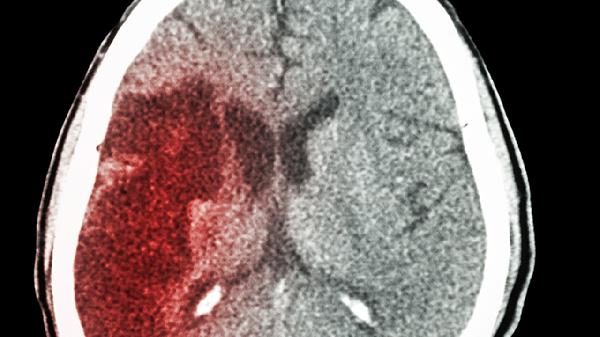

5、辅助治疗脑部疾病

在脑卒中后遗症、阿尔茨海默病等脑部疾病的综合治疗中,益智康脑丸可作为辅助用药。其神经保护作用能减轻氧化应激损伤,延缓病情进展。但需注意,该药物不能替代主要治疗手段,必须在神经科医生指导下配合其他治疗方案使用。